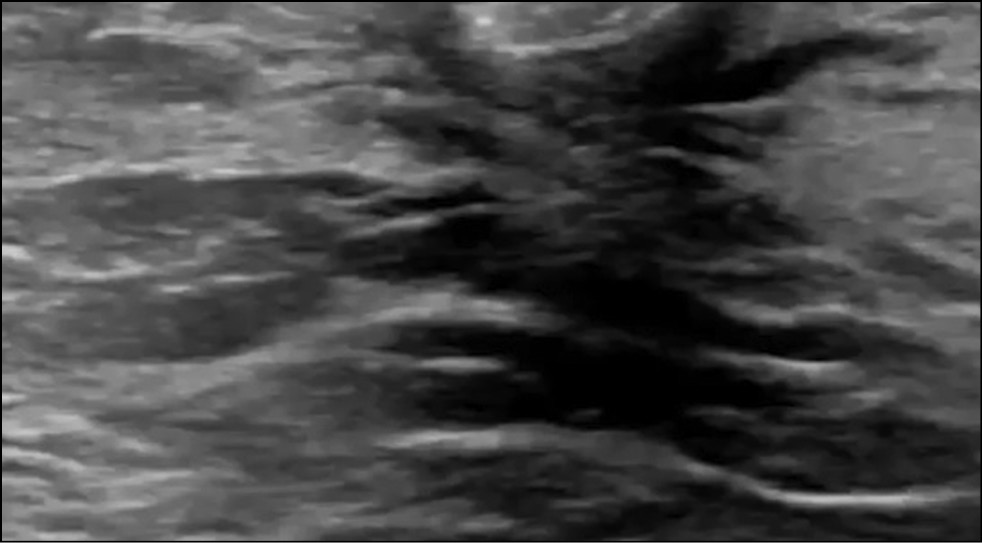

In a 38-year-old patient who had no complaints, a routine medical examination showed a left nipple inversion. Ultrasonography of the left breast revealed no abnormalities (Fig. 11). MRI with intravenous contrast (Fig. 12) showed asymmetric contrast accumulation with a retroareolar mass accumulating the contrast agent (inverted nipple). No focal breast pathology was detected.

Figure 11. Ultrasound image of the left breast with the inverted nipple.

Figure 12. Magnetic resonance imaging (subtraction): a retroareolar mass with accumulation of contrast agent (inverted nipple, arrow).

Nipple inversion is a benign condition associated with the insufficient ability of the mesenchymal tissue to fix the nipple in the right position. [12] It occurs in 4% of women and men. Nipples are convex in 75% of women, flat in 23%, and inverted in 2%. MIP images are well suited for assessing the morphology and symmetry of the NAC. On postcontrast images, the nipple should be hypo- or isointense compared with the enhanced parenchymal tissue in the background. [12]

Nipple inversion, retraction, and asymmetry are normal but may also be indicative of pathology. In differential diagnosis, obtaining a detailed medical history, comparing with results of previous examinations, and providing ongoing monitoring are recommended.